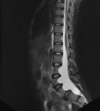

O que causa a DEGENERAÇÃO SUBAGUDA COMBINADA DA MEDULA?

Deficiência de b12 ou cobre; Ocorre o Acometimento dos funículos posteriores (grácil e cuneiforme) e porção posterior dos funículos laterais (tratos cortico-espinhais laterais) *por isso combinada; Lesão de hipersinal T2 na porção posterior da medula, com sinal do V invertido no corte axial; acomete mais comumente medula cervical e torácica.